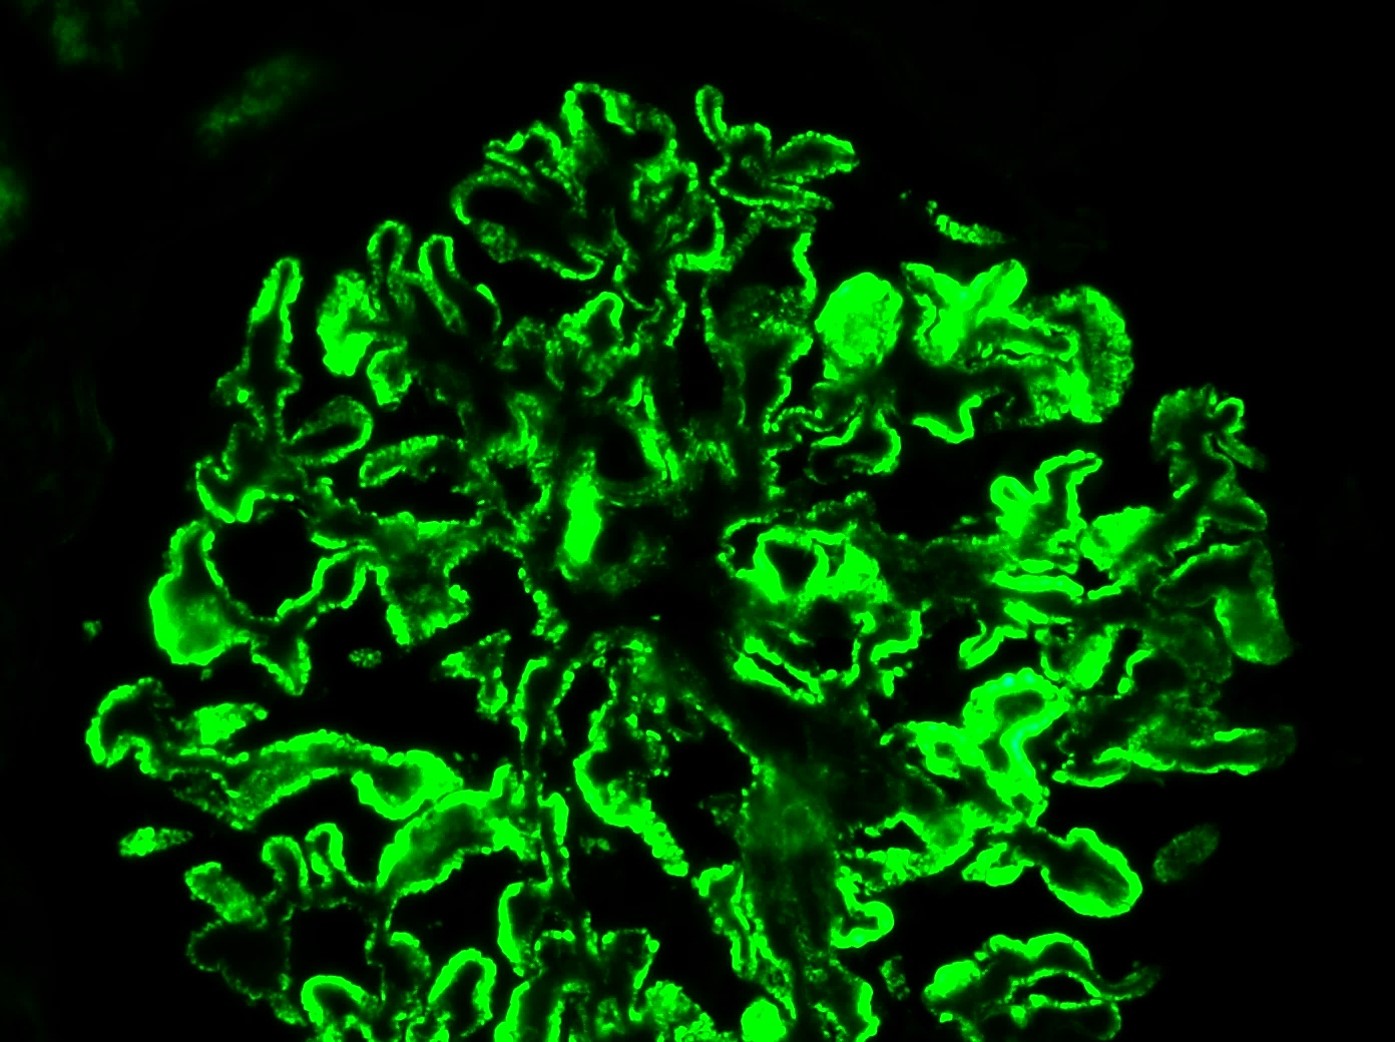

Immunofluorescence microscopy reveals a diffuse granular pattern of immunoglobulin G (IgG) staining along the GBM. The hallmark lesions on electron microscopy are subepithelial electron-dense deposits on the outer aspect of the GBM, effacement of the foot processes of the overlying podocytes, and expansion of the GBM by deposition of new extracellular matrix between the deposits (which are the "spikes" seen with the silver stain). Mesangial and/or subendothelial deposits of immunoglobulin are not seen in primary MN.